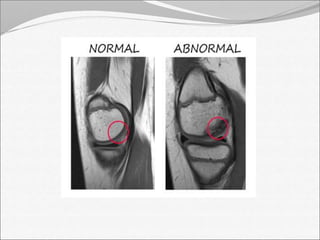

MRI findings:

• Synovial enhancement

• Perisynovial edema and joint effusion.

• Single or multiple radiolucent abscesses

• Assessment of the extent of tissue affected

MRI findings: •Synovial enhancement • Perisynovial edema and joint effusion. • Single or multiple radiolucent abscesses • Assessment of the extent of tissue affected